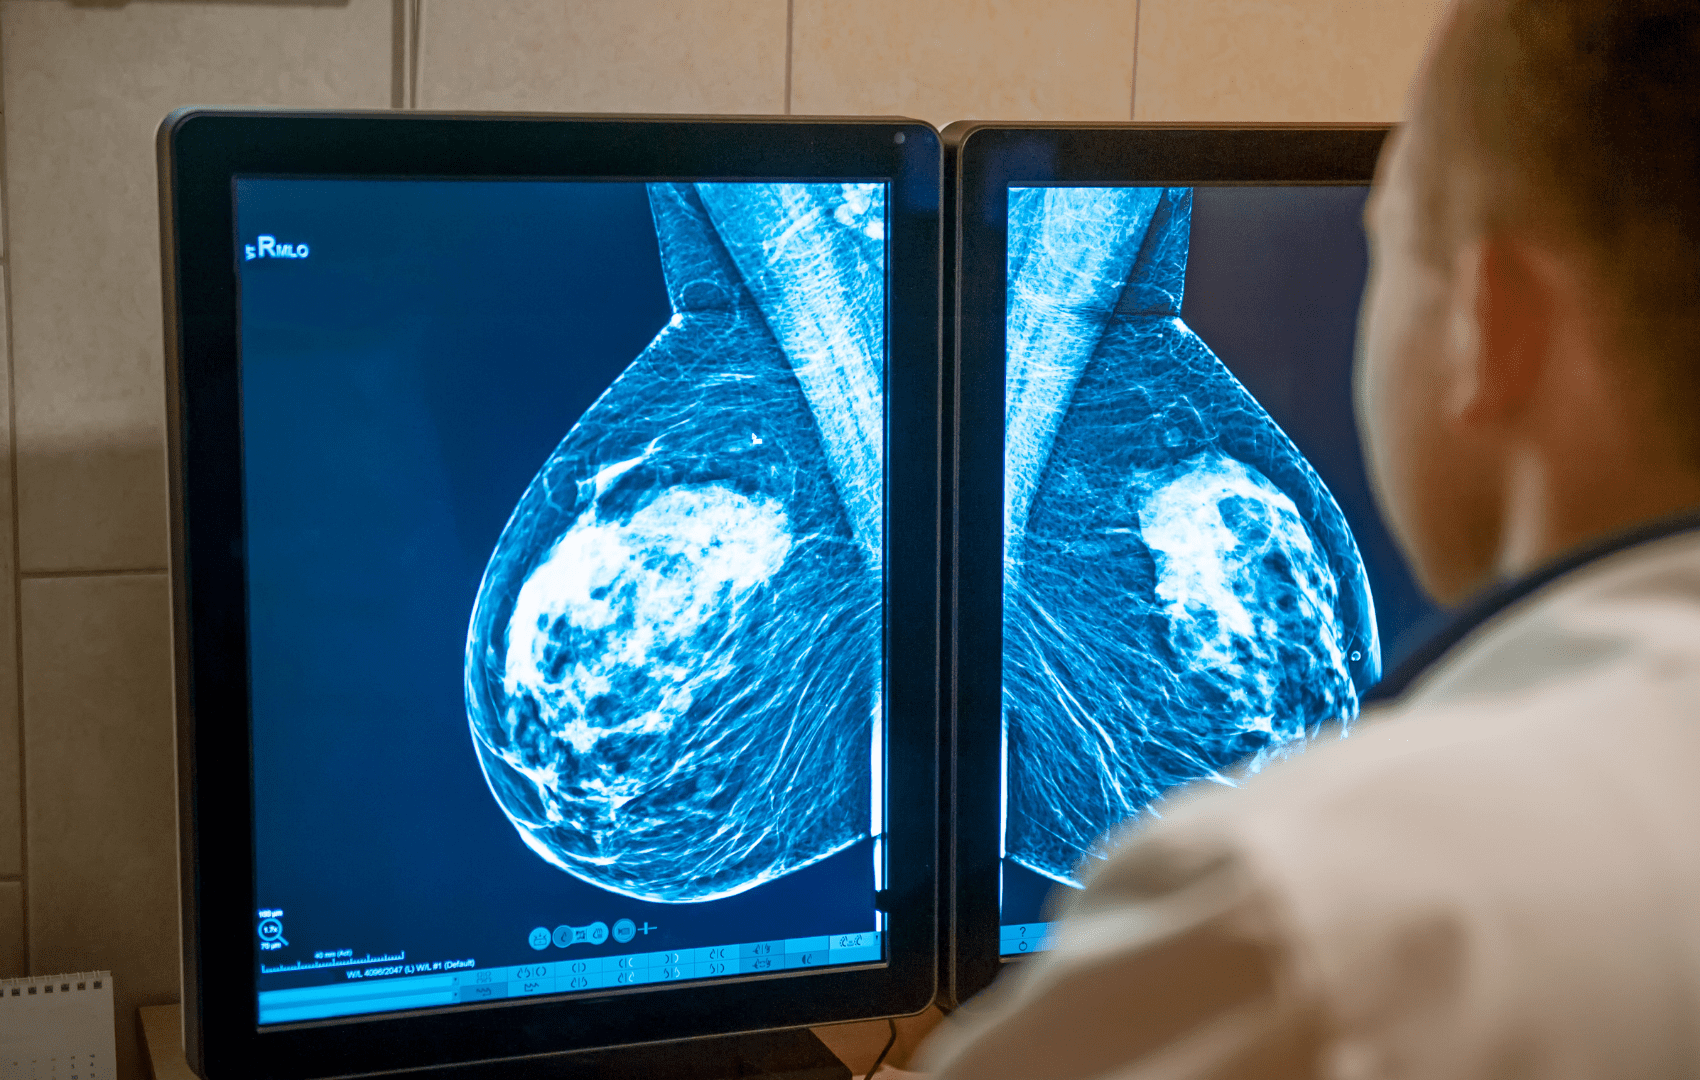

BIRADS: Entenda a Classificação das Imagens Mamárias

O BIRADS™ é um sistema que padroniza os laudos de mamografia, ultrassonografia e ressonância magnética das mamas, auxiliando radiologistas a categorizar achados e orientar condutas médicas.

O BIRADS™, sigla para Breast Imaging Reporting and Data System, é um sistema internacional desenvolvido pelo Colégio Americano de Radiologia (ACR). É uma ferramenta de comunicação entre radiologistas e clínicos, usada para:

O radiologista classifica os achados em uma escala de 0 a 6, sendo que cada número corresponde a um risco diferente de câncer e recomendações específicas.